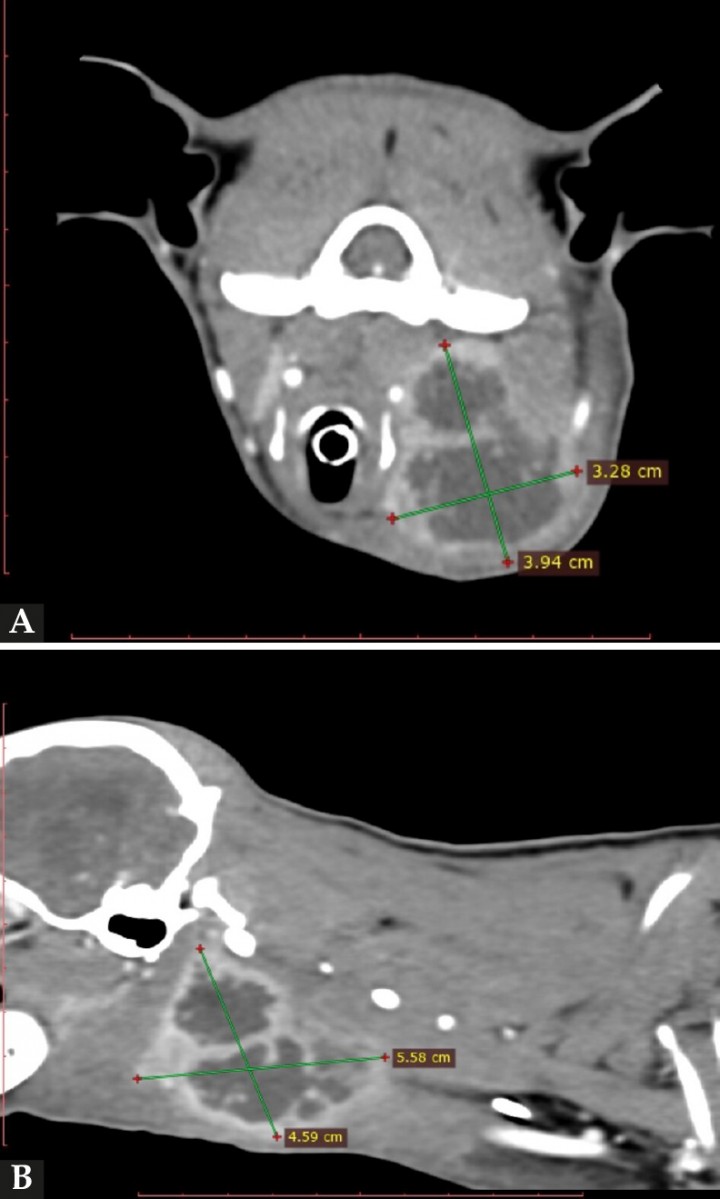

Se realizó una ecografía cervical que mostró un severo incremento del linfonodo (LN) retrofaríngeo izquierdo (3,9 x 1,9 cm), con parénquima heterogéneo y presencia de dos cavidades con contenido hipoecoico con zonas levemente hiperecoicas (Fig. 2). La interpretación fue linfadenitis o absceso linfonodal (de origen desconocido o secundario a cuerpo extraño). Posteriormente, se realizó un estudio de tomografía computarizada, el cual confirmó que la masa cervical tenía origen en el LN retrofaríngeo izquierdo. Además, se confirmó una linfadenomegalia ipsilateral (submandibular, cervical) (Fig. 3), la cual había sido observada durante el examen ecográfico. No se evidenció la presencia de ningún cuerpo extraño tomodensitométricamente visible.

<p>(<strong>A</strong>) TC, corte axial. Nótese que la masa cervical tiene origen en linfonodo retrofaríngeo izquierdo. (<strong>B</strong>) TC, corte sagital. Véase la misma lesión, alcanzando un tamaño de 5,58 x 4,59 cm.</p>

Figura 3

(A) TC, corte axial. Nótese que la masa cervical tiene origen en linfonodo retrofaríngeo izquierdo. (B) TC, corte sagital. Véase la misma lesión, alcanzando un tamaño de 5,58 x 4,59 cm.